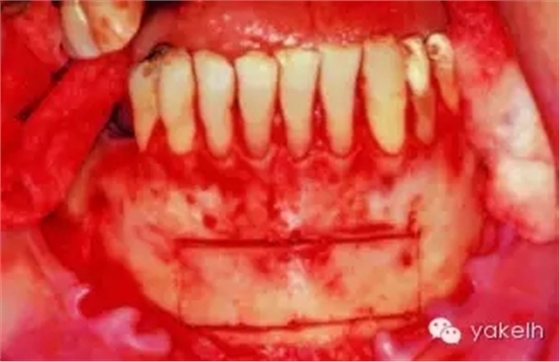

¤¤取骨入路容易是頦部供區(qū)的一個優(yōu)點。用含1∶100 000腎上腺素的2%利多卡因施行雙側(cè)下頜骨阻滯麻醉以及局部浸潤麻醉,可采用齦溝內(nèi)切口或者前庭溝切口暴露頦部。在雙側(cè)下頜尖牙之間,距離膜齦聯(lián)合處1cm的黏膜上做前庭溝切口(圖13.16,圖13.17)。限制切口向遠(yuǎn)中延伸可以降低損傷頦神經(jīng)的風(fēng)險。由于可以牽拉組織瓣,通過有限的切口也很容易到達(dá)頦部,前庭溝切口雖然很容易達(dá)頦部,但會造成更多的軟組織出血,還有可能形成口內(nèi)疤痕。當(dāng)有黏膜牙齦的缺損時,不能采用齦溝內(nèi)入路,因為這可能導(dǎo)致牙齦的退縮。齦溝內(nèi)切口應(yīng)該延長至雙側(cè)前磨牙區(qū)域(圖13.18)。翻起黏骨膜瓣,暴露雙側(cè)頦孔以及下頜骨下緣(頦點),在下頜骨的基底部,還需要額外的局部麻醉來阻滯頸神經(jīng)支配。

圖13.16 在雙側(cè)尖牙之間的黏膜上,做前庭溝切口。

圖13.17 通過前庭溝切口,翻起黏骨膜瓣,暴露下頜骨頦部。